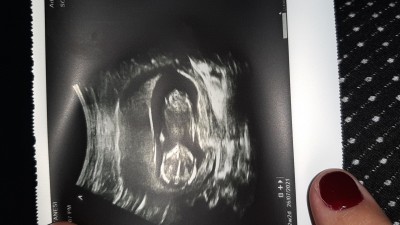

Merhaba 2. Bebeğime hamileyim 14 haftaligim ama doktor hala cinsoyetini soylemedi tahmn edebilen varmi resim koyuyorum.

Gebelik haftası 14

Erkeğe benziyor :) hayırlısı olsun

Burda arkası dönğk sadece popo kemiği görünüyor. Bacak arasının görünmesi lazım

Sağlıklı sıhhatli olsun erkeğe benziyor sanki :)

Kız bebek yapısı rabbim gönlüne göre versin